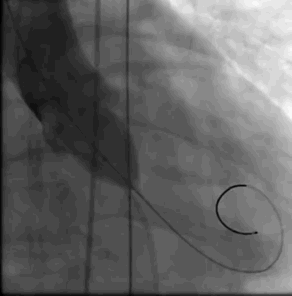

根据支架形态,此次选择BaIt23球囊后扩

瓣膜释放完成左右冠显影良好 瓣膜最终形态

L26号瓣膜释放,BaIt23预后扩,几乎无瓣周漏,压差解除